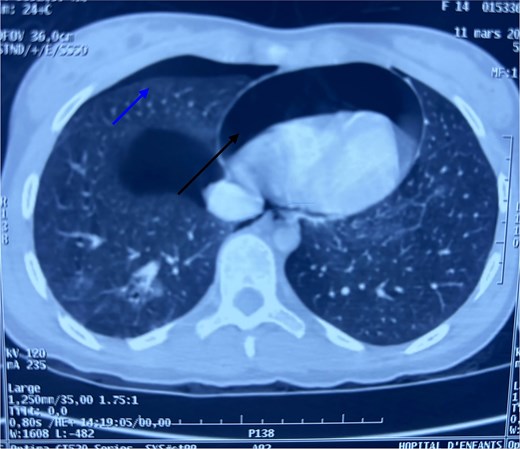

After hemodynamic stabilization, an emergency full-body computed tomography (CT) scan was performed, revealing a minimal pneumothorax, a significant pneumopericardium (Fig. 1), multiple pelvic fractures, and a vertebral fracture at the L3 level (Fig. 2). Blood tests showed a hemoglobin level of 8 g/dL, prompting transfusion of two units of packed red blood cells. Following the onset of chest pain, a percutaneous decompression of the pneumopericardium was performed, resulting in rapid clinical improvement. The patient was then admitted to the intensive care unit for close monitoring. She subsequently underwent surgical osteosynthesis from L2 to L4.

Axial chest CT scan showing pneumopericardium (lower arrow) and pneumothorax (upper arrow).